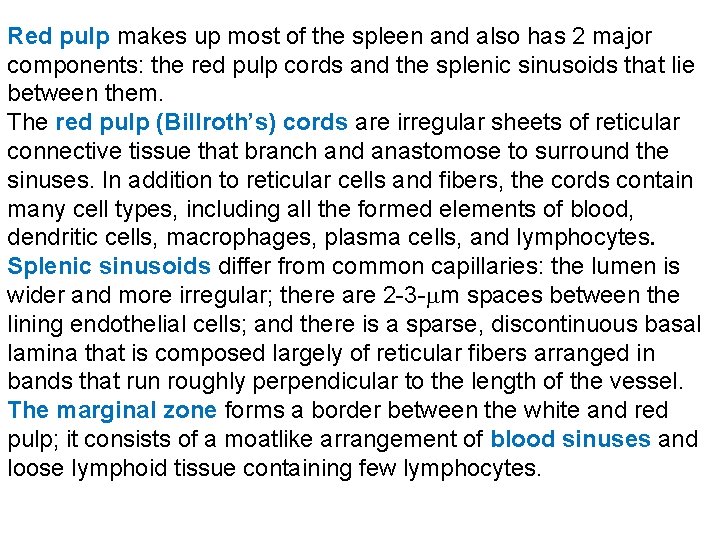

Red pulp makes up most of the spleen and also has 2 major components: the red pulp cords and the splenic sinusoids that lie between them. The red pulp (Billroth’s) cords are irregular sheets of reticular connective tissue that branch and anastomose to surround the sinuses. In addition to reticular cells and fibers, the cords contain many cell types, including all the formed elements of blood, dendritic cells, macrophages, plasma cells, and lymphocytes. Splenic sinusoids differ from common capillaries: the lumen is wider and more irregular; there are 2 -3 - m spaces between the lining endothelial cells; and there is a sparse, discontinuous basal lamina that is composed largely of reticular fibers arranged in bands that run roughly perpendicular to the length of the vessel. The marginal zone forms a border between the white and red pulp; it consists of a moatlike arrangement of blood sinuses and loose lymphoid tissue containing few lymphocytes.

Open and closed theories of splenic circulation. Blood in the capillaries reaches the sinusoid lumens by two ways. The closed theory holds that the capillary walls are continuous with the walls of the sinusoids and that the capillaries empty directly into the sinusoid lumens. The open theory holds that the capillaries end abruptly in the red pulp cords and that blood reaches the sinusoid lumens by percolating through the cords and passing through openings in the sinusoid walls. For humans, current evidence favors the open theory. Central arteries and open blood circulation are unique feature for the spleen. Functions: 1. Filtration of blood. 2. Lymphocyte production (lymphopoiesis). 3. Destruction of worn red blood cells 4. Extramedullary hematopoiesis.